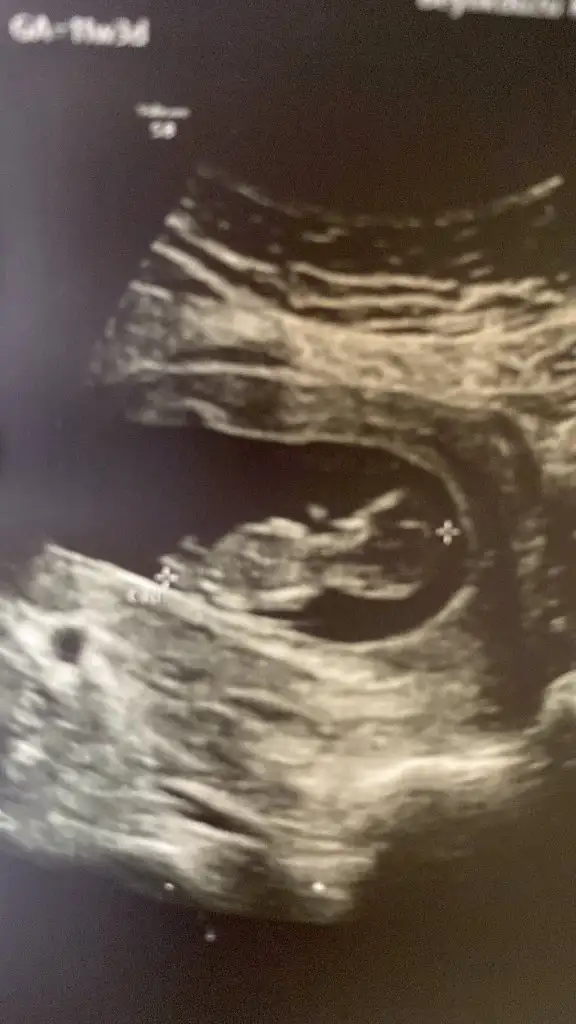

Erkek gibi sankiBuna da bakar mısınız 12+6Ikra meyra

Çok teşekkür ederim vakit ayırıp baktığınız için 1 ay sonrasına gün attı doktorum kesinlesir kesinlesmez paylasicamKiz görünüyor